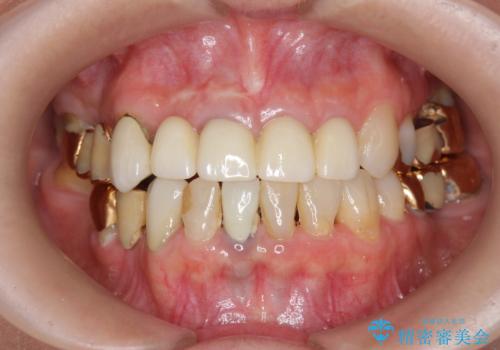

- 前歯の痛み・排膿・ぐらつきの改善を求めて来院されました。

視診・X線写真検査より根尖性歯周炎が認められ再治療が必要な状態です。

再根管治療を行うべくクラウン除去を行ったところ、右上側切歯に保存不可能な垂直性の破折が認められたため抜去が必要になりました。

即切歯の抜歯を行う場合犬歯を含めたブリッジによる補綴計画を立てることが多いですが、今回は犬歯から大臼歯にかかる大きなブリッジが既に装着されていたため予算とご希望を相談し前歯のみの延長ブリッジ補綴で治療を行っていくこととしました。